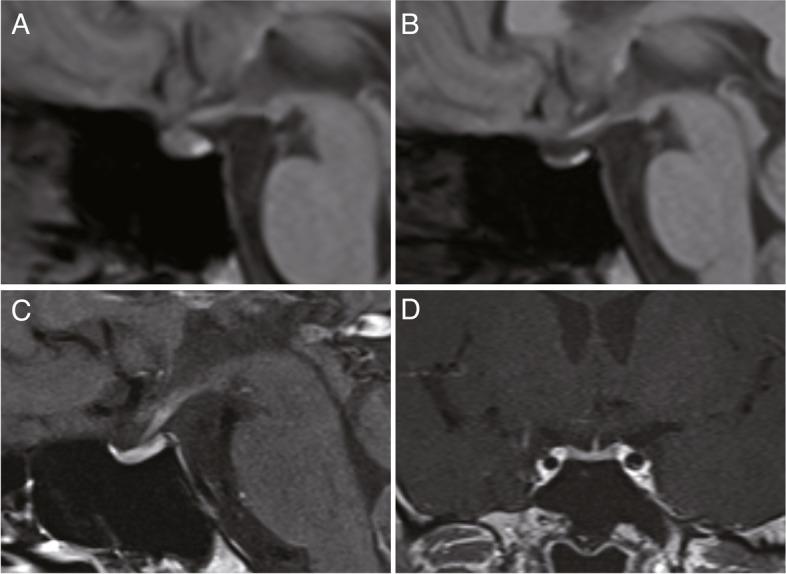

A healthy 31-year-old man received the BNT162b2 SARS-CoV-2 mRNA vaccine. The first injection was uneventful. One day after the second injection, he noticed general fatigue and fever. In the following several days, he additionally developed headaches, nausea, and diarrhea. Four days after the vaccine injection, he visited a hospital with worsening of these symptoms. Physical examination revealed slight disorientation but no other deficits. Laboratory tests revealed hyponatremia, hypoglycemia, and extremely low plasma ACTH and serum cortisol levels (ACTH < 1.5 pg/ml, cortisol 1.6 μg/dl). He was diagnosed with adrenal crisis and was emergently treated with hydrocortisone. The symptoms responded well and he recovered within a few days. Magnetic resonance images after the replacement with hydrocortisone revealed an atrophic pituitary gland. The patient was referred to our tertiary hospital for further endocrinological examination. Pituitary endocrine load tests revealed isolated adrenocortical response deficiency. After other clinical assessments, he was diagnosed as having isolated ACTH deficiency. After initiation of hydrocortisone replacement, there has been no recurrence of symptoms related to adrenocortical insufficiency nor involvement of other pituitary functions.

一名健康的 31 岁男性接种了 BNT162b2 SARS-CoV-2 mRNA 疫苗。第一次注射没有出现任何问题。第二次注射后一天,他注意到全身疲劳和发烧。在接下来的几天里,他还出现了头痛、恶心和腹泻。疫苗注射后第四天,他因症状加重去了医院。体格检查发现有些定向障碍,但无其他缺陷。实验室检查显示低钠血症、低血糖和极低的血浆 ACTH 和血清皮质醇水平(ACTH<1.5pg/ml,皮质醇 1.6μg/dl)。他被诊断为肾上腺危象,并紧急接受了氢化可的松治疗。症状得到了很好的缓解,他在几天内康复。氢化可的松替代治疗后的磁共振成像显示垂体萎缩。患者被转至我们的三级医院进行进一步的内分泌检查。垂体内分泌负荷试验显示孤立性肾上腺皮质反应缺陷。在进行其他临床评估后,他被诊断为孤立性 ACTH 缺乏症。开始使用氢化可的松替代治疗后,未再出现与肾上腺皮质功能不全相关的症状,也未出现其他垂体功能受累。